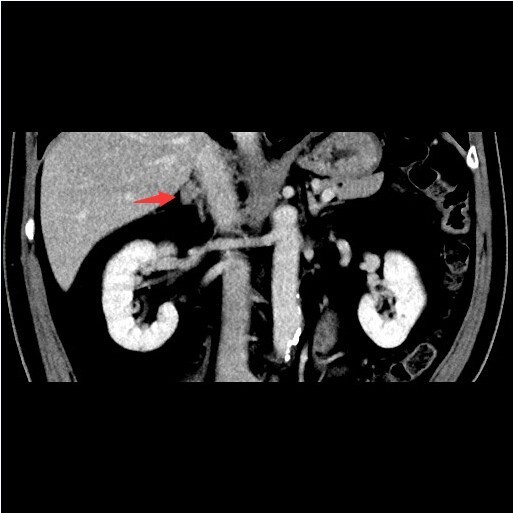

查体::血压:140/80mmHg。双肾区无红肿、隆起,无叩痛,双侧肋脊点、肋腰点无压痛。 辅查:双肾上腺CT提示:右侧肾上腺结节,考虑腺瘤可能性大,右侧小囊肿,肝内多发囊肿。

随访:术后病理示:考虑为肾上腺皮质腺瘤。 讨论:肾上腺腺瘤是来源肾上腺皮质的腺瘤,根据临床表现不同,临床分为无功能性腺瘤、功能性腺瘤(又分为Cushing腺瘤和Conn腺瘤),本例患者具有乏力、低血钾和高血压等醛固酮增多症表现,应属于Conn腺瘤。该类腺瘤一般表现为肾上腺区的孤立性小肿块,边界清楚,大小一般不超过2cm,由于富含脂质,CT平扫密度接近于水样密度,增强扫描轻度强化,本例的CT影响表现基本符合。